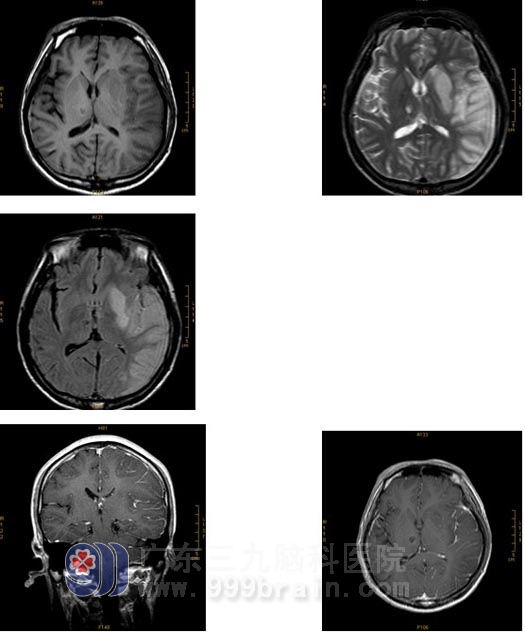

磁共振检查所见:

▲左大脑中动脉供血区(左侧额颞叶及左侧基底节区)大片梗塞灶,双侧丘脑小片状梗塞灶,MRA检查示左侧大脑中动脉闭塞。